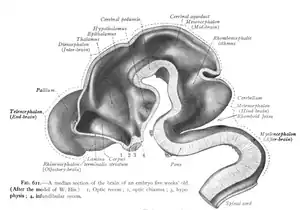

Late in the fourth week, the superior part of the neural tube bends ventrally as the cephalic flexure at the level of the future midbrain—the mesencephalon.[24] Above the mesencephalon is the prosencephalon (future forebrain) and beneath it is the rhombencephalon (future hindbrain).

The optical vesicle (which eventually becomes the optic nerve, retina and iris) forms at the basal plate of the prosencephalon. The alar plate of the prosencephalon expands to form the cerebral hemispheres (the telencephalon) whilst its basal plate becomes the diencephalon. Finally, the optic vesicle grows to form an optic outgrowth.